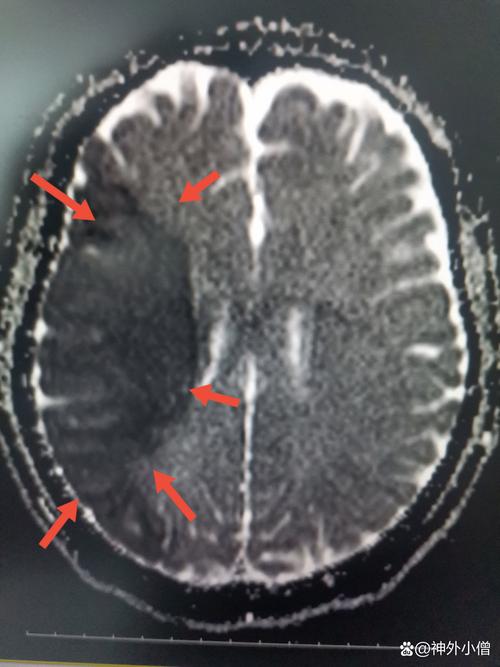

这是一个非常严肃的医学问题,答案是:是的,右侧侧脑旁的脑梗通常是比较严重的,需要立即就医。

“侧脑旁”这个描述指的是病变位置紧邻侧脑室,这个位置的脑梗之所以严重,主要有以下几个关键原因:

大脑的白质区域(侧脑室周围主要是白质)是连接不同脑区的重要“高速公路”,由上行的感觉纤维和下行的运动纤维组成,侧脑室旁区域尤其重要,它包含了:

- 皮质脊髓束: 这是控制对侧肢体运动最关键的通路,如果这里的梗塞,会导致对侧(左侧)身体出现严重的偏瘫,可能包括整个左臂、左腿无法活动,肌肉张力增高(痉挛)。

- 皮质脑干束: 控制对侧的面部表情和吞咽功能,损伤会导致中枢性面瘫(左侧鼻唇沟变浅,口角向右歪斜)和吞咽困难,后者极易引发误吸性肺炎,是脑梗后常见的并发症和死亡原因。

- 感觉传导束: 损伤会导致对侧肢体感觉障碍,如麻木、针刺感、感觉减退或消失。

- 认知相关纤维: 梗塞范围如果较大,累及额叶、颪叶的连接纤维,还可能导致认知功能下降、记忆力减退、注意力不集中等问题。

- 梗塞面积大小: 梗塞范围越大,症状越重,预后越差,CT或MRI上显示的梗塞体积是判断预后的重要指标。